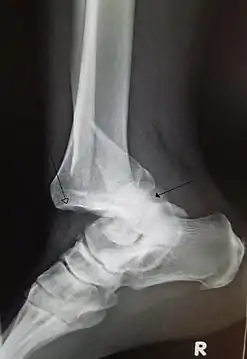

Сильний біль у ділянці вивихнутого суглоба, який посилюється при спробі ворухнути, відсутність руху у ньому. При огляді відзначають деформацію у ділянці суглоба, помітну при порівнянні його зі здоровим суглобом. При пальпації виявляють, що голівка суглоба знаходиться не на місці, а зміщена в сторону. Спроби провести пасивні рухи викликають сильний біль. Діагноз ставлять за допомогою рентгенологічного дослідження.